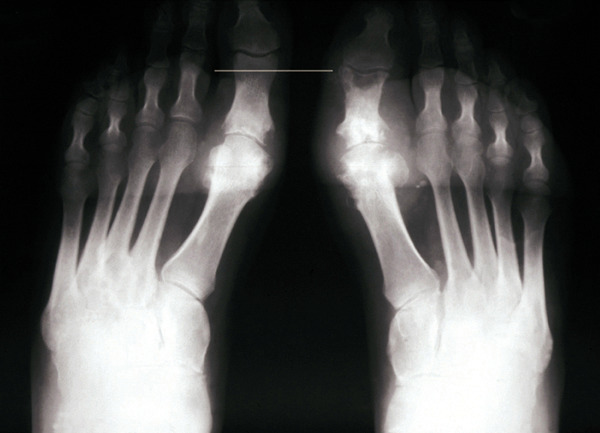

• une monoarthrite aiguë, touchant de façon privilégiée les articulations distales des membres inférieurs, en particulier la première métatarso-phalangienne ;

Le patient non traité par hypo-uricémiant peut développer une goutte polyarticulaire chronique caractérisée par des articulations douloureuses et gonflées en permanence, l’apparition de tophus (fig. 1) voire d’une arthropathie destructrice (fig. 2 et 3), et des manifestations rénales (lithiase rénale, le plus souvent uratique, néphropathie interstitielle …).